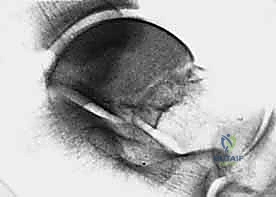

2. التصوير الإشعاعي (الأشعة السينية - X-rays)

هي الخطوة الأولى. تُطلب صور من زوايا متعددة:

* الرؤية الأمامية الخلفية (AP).

* الرؤية الجانبية (Lateral).

* رؤية الهاون (Mortise view).

* رؤية كانال (Canale View): وهي وضعية تصوير خاصة جداً لتقييم عنق الكاحل وتحديد درجة الإزاحة بدقة.

3. التصوير المقطعي المحوسب (CT Scan) - المعيار الذهبي

في عيادة الأستاذ الدكتور محمد هطيف، يُعتبر التصوير المقطعي المحوسب ثلاثي الأبعاد (3D CT Scan) إجراءً روتينياً وحتمياً لأي كسر في عظم الكاحل. توفر الأشعة المقطعية تفاصيل دقيقة للغاية عن خطوط الكسر، مدى التفتت (Comminution)، وحجم الإزاحة المفصلية التي لا يمكن رؤيتها بالأشعة السينية العادية. بناءً على هذه الصور، يقوم الدكتور هطيف ببناء استراتيجية الجراحة (أين سيفتح، ما نوع الشرائح والمسامير التي سيستخدمها، وكيف سيعيد بناء العظم).